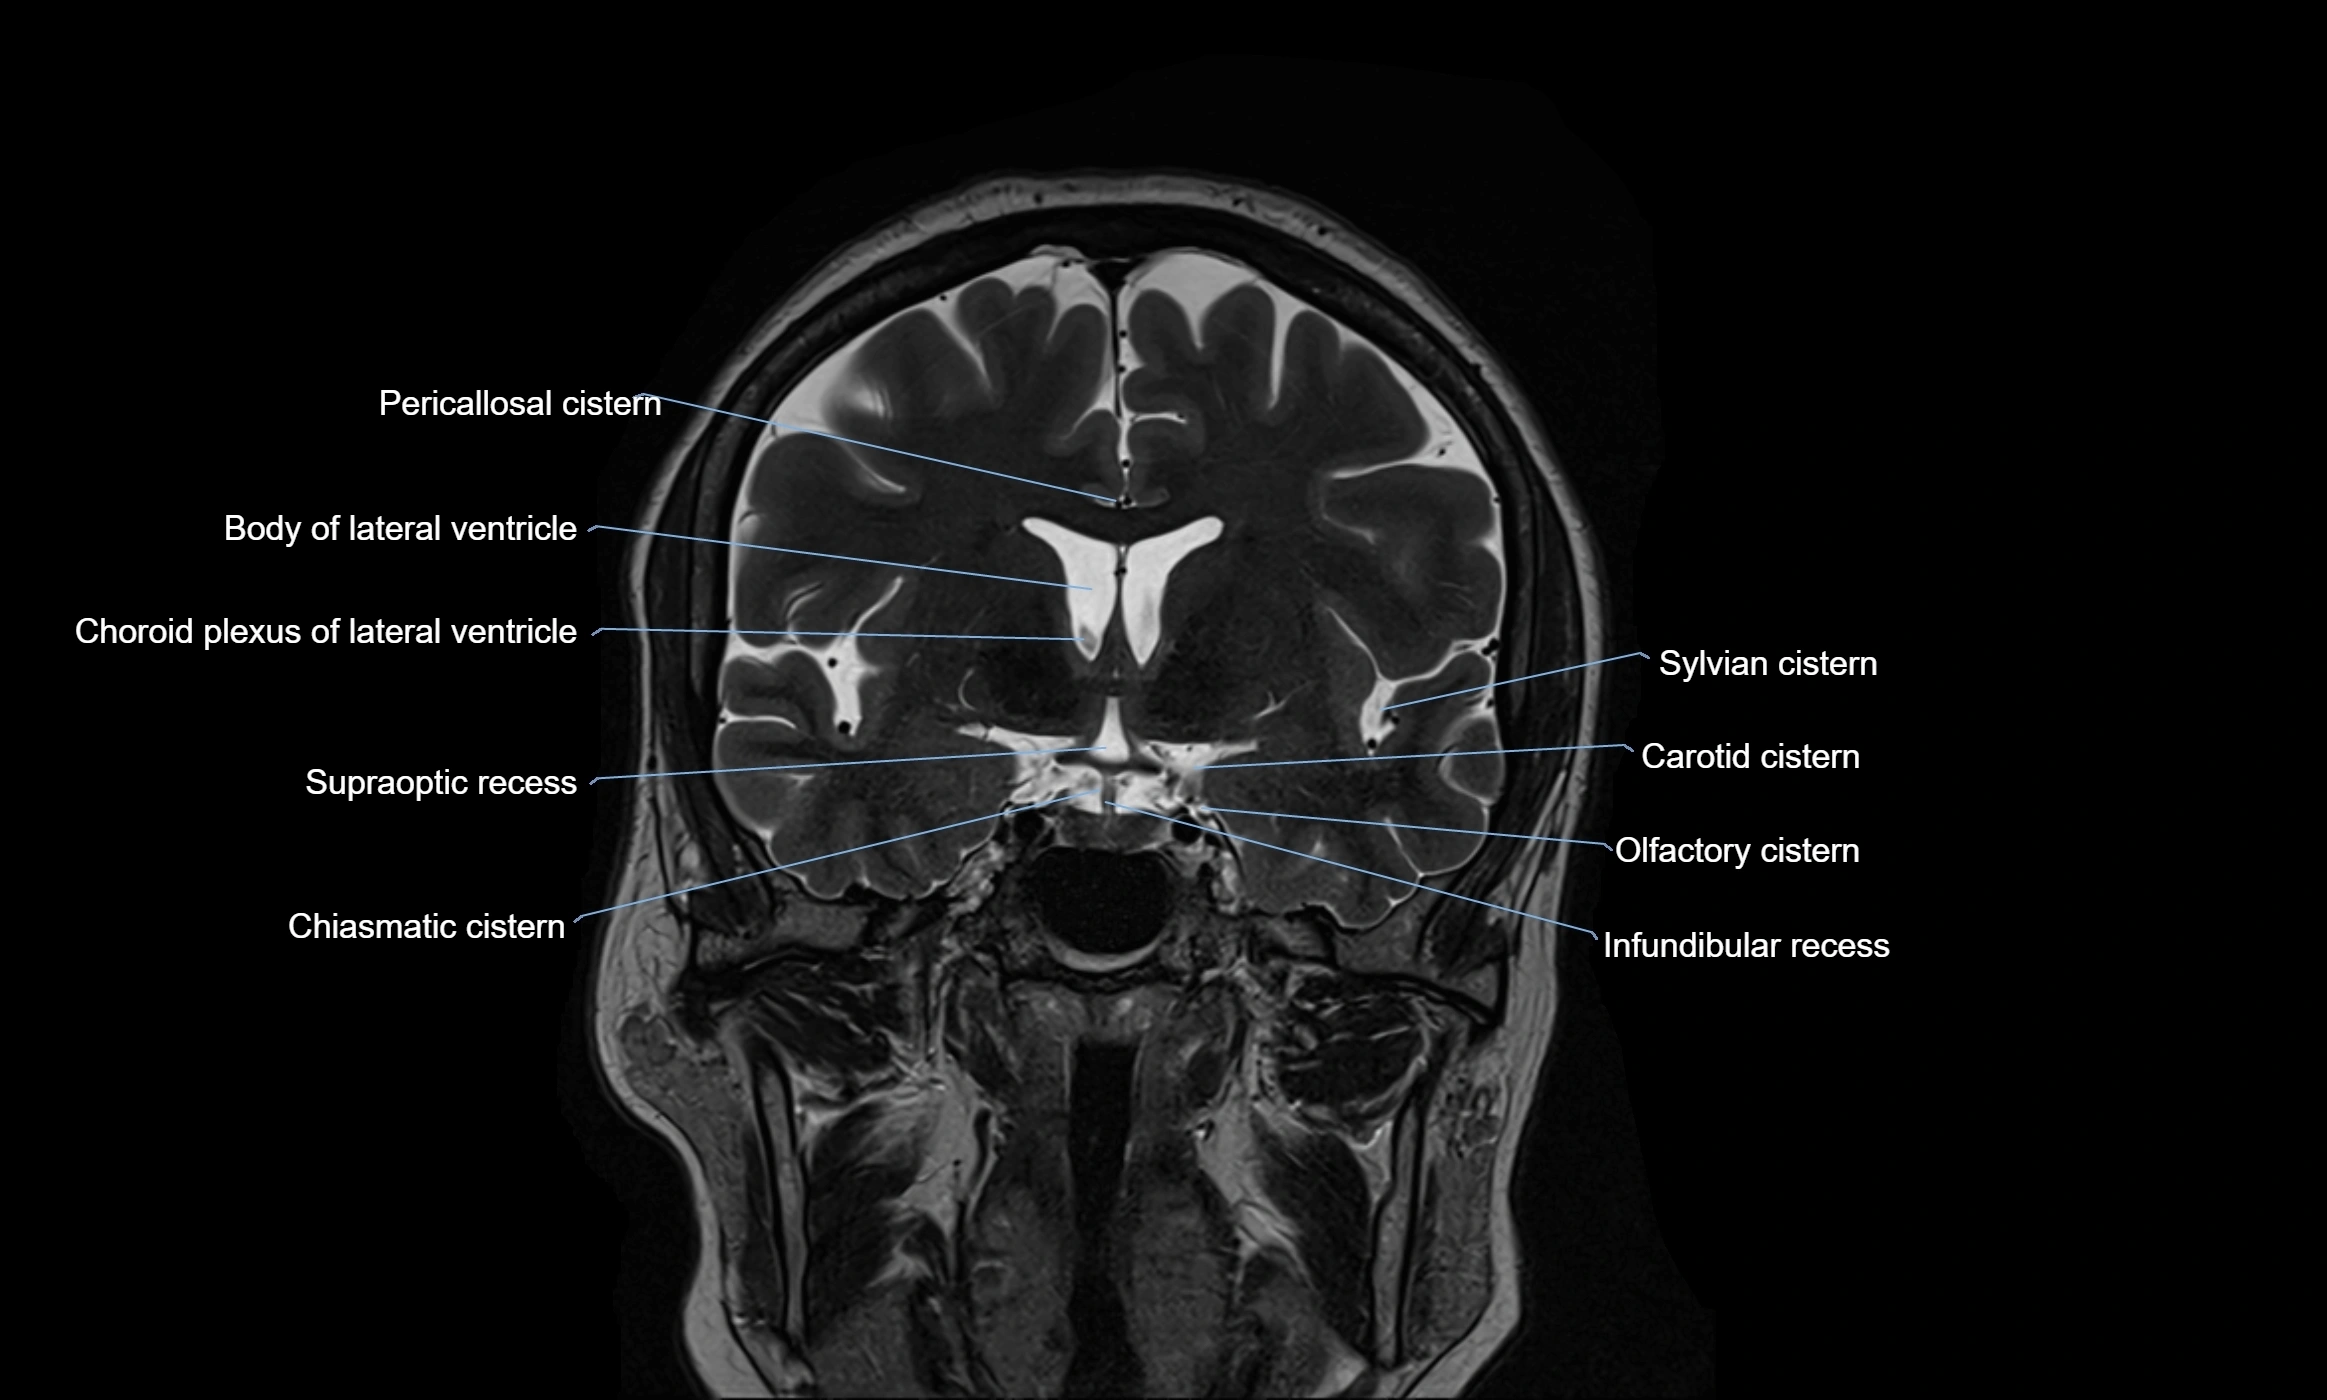

MRI images

image